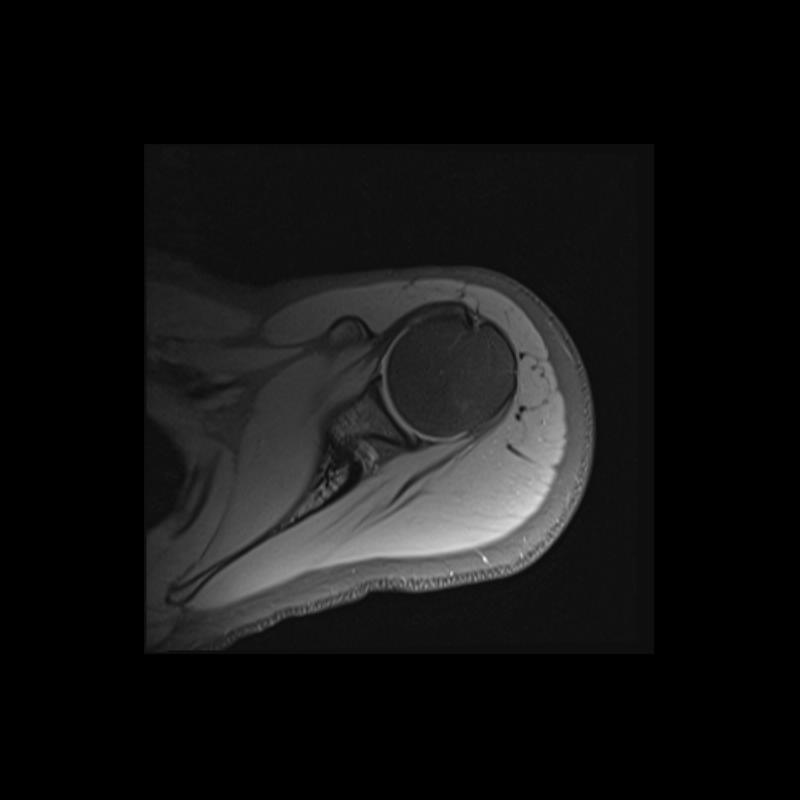

Shoulder MRI Anatomy